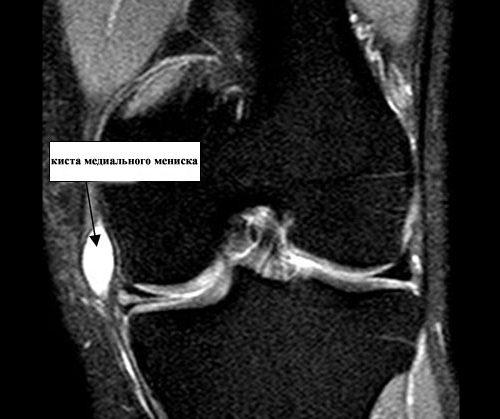

Различают внутренний (медиальный) и внешний (латеральный) мениск. Они соединены между собой поперечной связкой. Киста наружного мениска (параменискальная) встречается у пациентов намного чаще, чем медиального. Такая ситуация связана с тем, что внешний мениск более подвижный. Он реже разрывается, но более подвержен образованию кист.

Киста латерального мениска выпячивается сзади от наружной боковой связки, а медиального — спереди.

- магнитно-резонансная терапия.